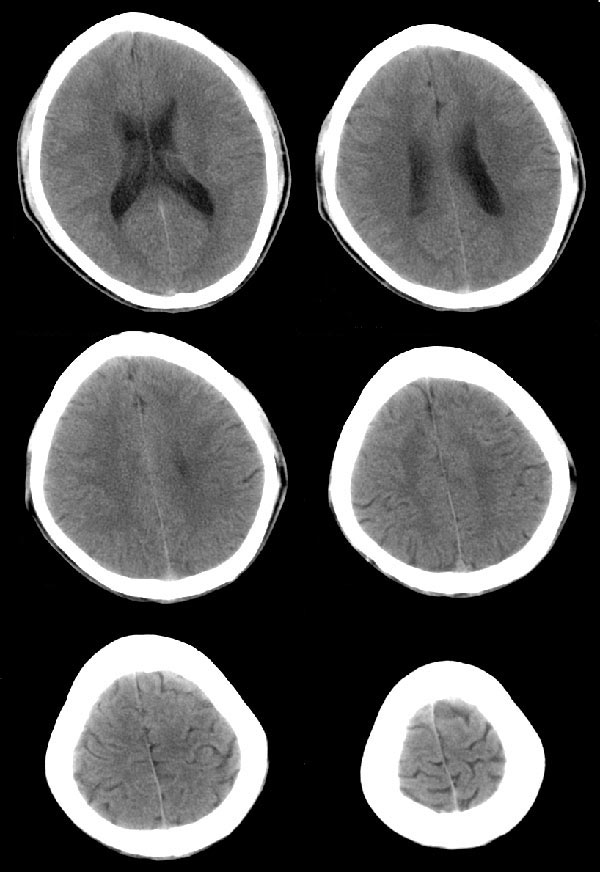

20岁男性患者,平时偶有头痛而无其他不适,现因持续头痛服药后无缓解而来院就诊。

松果体区占位继发轻度脑积水?该患者有ct资料,我已发上。

考虑松果体囊肿。